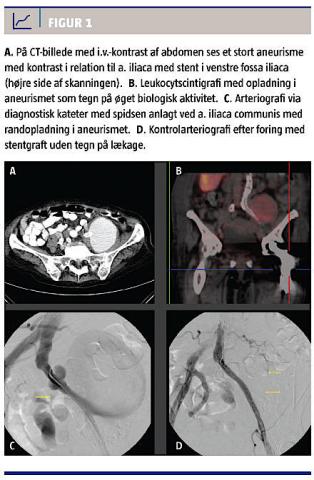

En 85-årig kvinde med kronisk lymfatisk leukæmi og tidligere emboli i venstre ben fik konstateret en absces til venstre i det lille bækken. Den blev dræneret, og en samsidig hydronefrose blev behandlet med JJ-kateter. Det venstresidige iliacasystem fandtes okkluderet. Pga. venstresidig underekstremitetsiskæmi (claudicatio) blev der et år senere planlagt ballondilatation af det modsidige højre iliacasystem med indsættelse af en femerofemoral cross-over-bypass fra højre til venstre femoralpulsåre. Interventionen endte dog som en dristig rekanalisering af begge iliacasystemer med indsættelse af lange kissing-stent. Fire år efter primærinterventionen konstaterede man ved en CT en 8 cm stor pulserende udfyldning i nederste venstre side af abdomen (Figur 1A). Biokemisk var patienten præget af sin leukæmi med følgende koncentrationer: hæmoglobin 3,9 mmol/l, leukocyt 113 mia./l og C-reaktivt protein 6 mg/l.

En leukocytscintigrafi viste opladning i aneurismet (Figur 1B), og ved bloddyrkninger fandt man koagulasenegative stafylokokker, hvilket er foreneligt med et mykotisk aneurisme. Aneurismet udgik fra den stentbehandlede venstre a. iliaca communis og blev ukompliceret ekskluderet ved indsættelse af en stentgraft (Fluency 9 mm bred og 8 cm lang coated stent, Figur 1C + D). Patienten blev samtidig sat i antibiotisk langtidstabletbehandling med moxifloxacin 400 mg × 1 dagl. Ved kontrol seks måneder senere var der ved UL-skanning puls i venstre lyske og intet flow i aneurismet, og en efterfølgende CT viste tydelig skrumpning af aneurismet. Patienten gik ad mortem et år efter indsættelsen af stentgraften pga. opblussen i leukæmien.